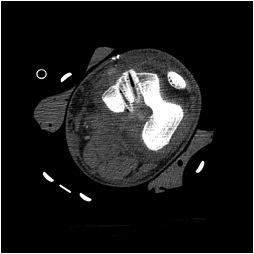

CT demonstrating ACL and PCL tunnels

Xray following PCL reconstruction, LCL and politeus reconstruction. CT demonsrating popliteus and LCL tunnels